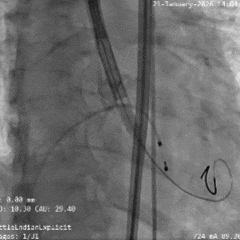

术中影像

双窦展开位根部造影

瓣叶狭窄明显,无明显反流

直头导丝顺利跨瓣

猪尾导管测量跨瓣压差约70mmHg

18mm球囊预扩,球囊上下滑动,无腰无漏,左冠显影,右冠无显影

输送系统顺利过弓

造影确认初始定位零位

瓣膜稳定展开

全展开位造影评估

瓣架呈直筒型,位置接近0位,少量反流

瓣膜缓慢脱钩,可见瓣膜实现自同轴,且无位移

脱钩后造影评估

瓣架形态佳位置可,冠脉显影,导丝压瓣可见反流

最终根部造影

撤出心室导丝后,反流明显减少